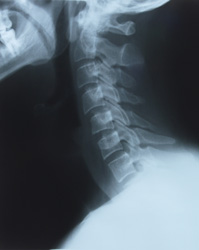

A subluxation is the result of spinal bones with improper motion or position affecting nerve communications between your brain and your body.What Are Subluxations?

A subluxation is a stress response. Muscles go into spasm. Spinal bones lock up. And adjacent nerves are choked or chafed. This interferes with the control and regulation of your body. This garbles communications between the brain and parts of your body.Distorted nerve communications can be an underlying cause of many health problems beyond just headaches and back pain. For example, interference with nerve impulses going to or from your stomach: stomach problems.

Your nervous system controls every cell, tissue, organ and system of your body. These nerve impulses travel through your spine. So having a spine free of subluxations is essential for optimal health.